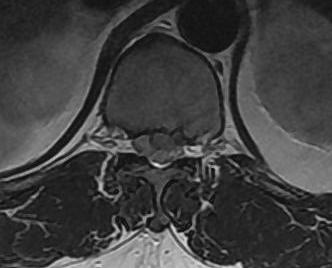

Present with intercostal radiculopathy or myelopathy

MRI

Very sensitive

- 40% incidence asymptomatic thoracic disc protrusion